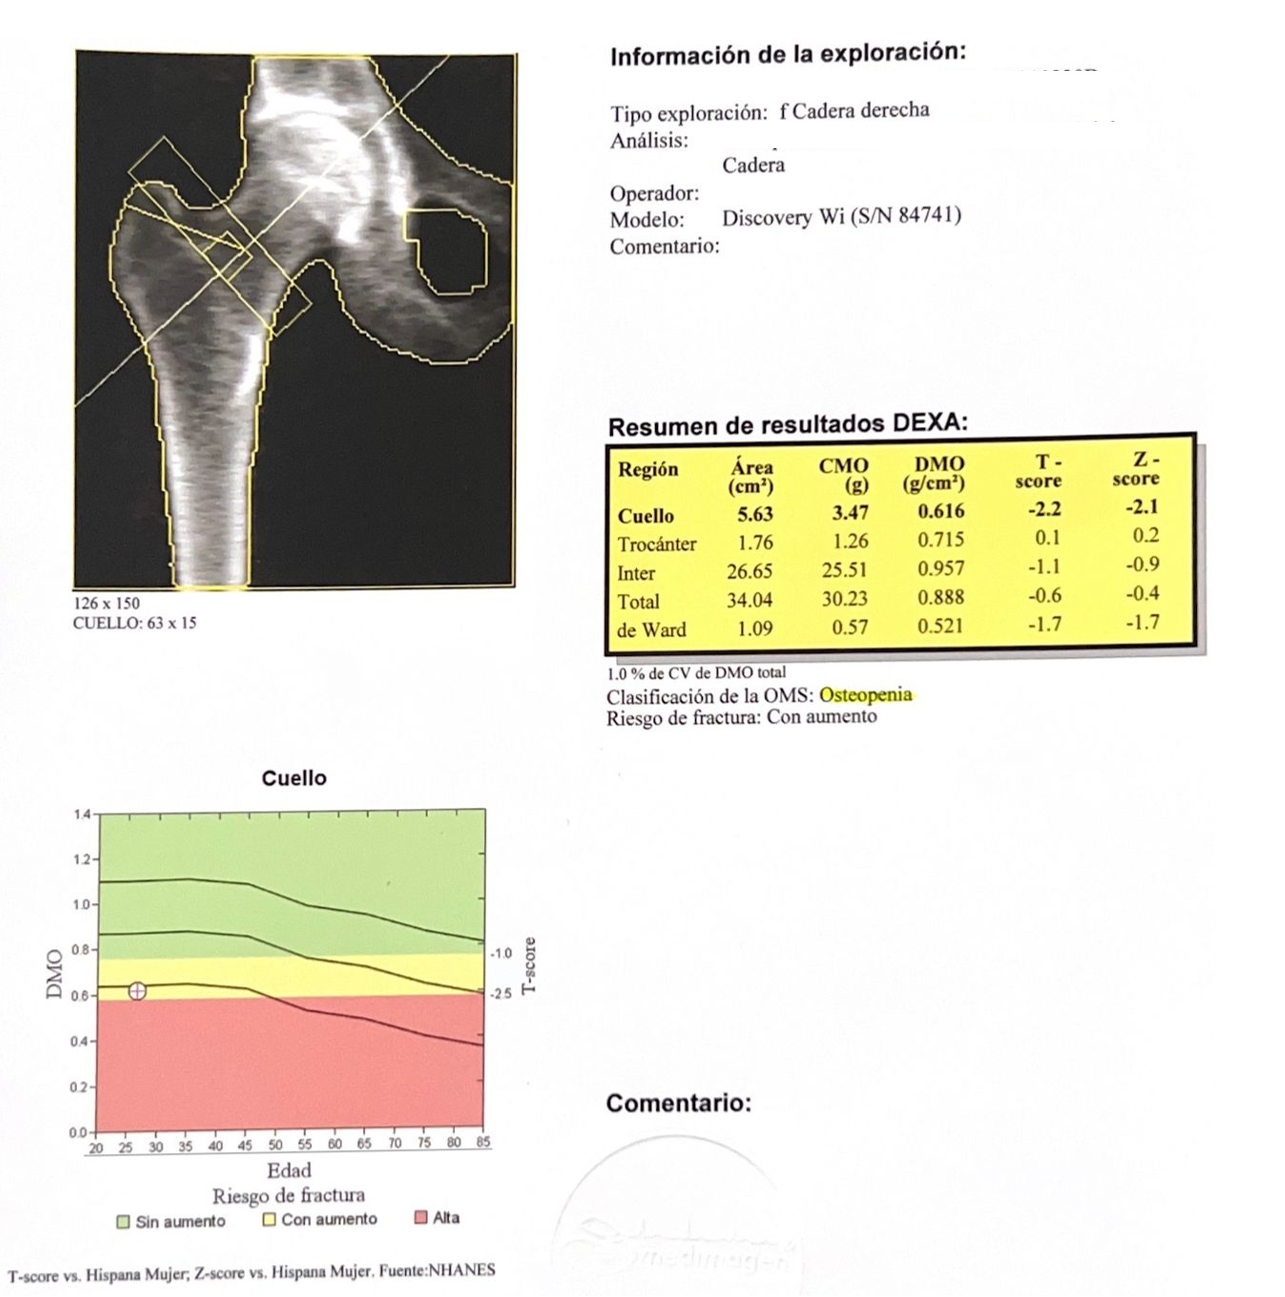

Por otra parte, debido a sus alteraciones endocrinas múltiples se solicitó también densitometría ósea de cadera, por dolor referido por la paciente encontrando los siguientes resultados.

Figura 4. Densitometría ósea de cadera, donde se diagnosticó de osteopenia

La osteopenia que presentó la paciente se atribuyó directamente a su enfermedad de hipotiroidismo e hipogonadismo, que provocan déficit hormonal sobre todo de estrógenos que resultan un factor protector para esta patología.